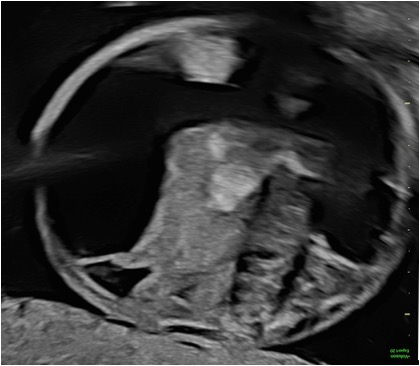

Caso 1 –

quesito Caso clinico Bove Jan 2026 copia